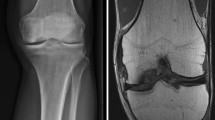

Healing was characterized by chronological progression in 4 stages (Fig. 1). After 3 months, stages 1, 2, 3 and 4 were represented 3, 3, 4 and 2 times, respectively; after 6 months, 0, 2, 2 and 8 times. Complete but irregular subchondral bone plate restoration was found in ten samples (Fig. 2). In these stage 4 samples, the central area showed an empty cavity (n = 3), a cavity lined by fibrous tissue and a centrally placed cystic vacuolization (n = 3), a cavity fully filled with fibrous tissue (n = 2) or a central area almost totally filled with dense bone (n = 2). These latter two samples without cavitary lesion formation centrally showed fibrocartilage remnants and thus were not fully filled with mineralized bone.

Subchondral bone plate restoration stages. In these Safranin O/Fast Green stained samples, mineralized bone and fibrous tissue appear bluish green, whereas (fibro)cartilage appears red. Scale bars represent the diameter of the initial osteochondral defect. a In stage 1 (n = 3), the defect was continuous with the synovial cavity, with no signs of defect bridging. Notice the extensive (fibro)cartilage collapse (white horizontal arrows) and erosion of bone outside the perimeters of the initially created defect (black vertical arrows). b In stage 2 (n = 5), fibrous tissue bridging or minor circumferential subchondral bone plate restoration was present. The main difference with stage 1 was the formation of fibrous strands in an attempt to partially close the created defect (white vertical arrow). Again, collapse of (fibro)cartilage (white horizontal arrow) and subchondral bone (white arrowhead), coupled to osseous erosion (black vertical arrows), was seen frequently. Already, the first signs of a central irregularly shaped cavitary lesion were seen. This lesion was either empty or filled with connective tissue. In some samples, central vacuolization of the fibrous tissue was present. c In stage 3 (n = 6), there was still inward collapse of subchondral bone and (fibro)cartilage. Progressive subchondral bone plate restoration was observed. Notice the evident subchondral bone sclerosis (black arrowhead). The central cavitary lesion, which was nearly closed, either was lined with fibrous tissue or showing exposed bone. d In stage 4 (n = 10), there was complete sclerotic osseous bridging of the defect, with mostly a concave fibrocartilaginous articular surface, and a central cavitary lesion which was either empty or filled with fibrous tissue. Again, cartilage flow and subchondral bone sclerosis were present

Subchondral bone plate restoration in stage 4 Safranin O/Van Kossa stained samples. Mineralized bone appears black, and (fibro)cartilage and fibrous tissue appear red. Scale bars represent the diameter of the initial osteochondral defect. The subchondral bone plate was characterized by irregular restoration, compromised by fibrocartilage flow (white arrows), the underlying cavitary lesion (black arrow) and subchondral bone plate advancement (arrowheads)